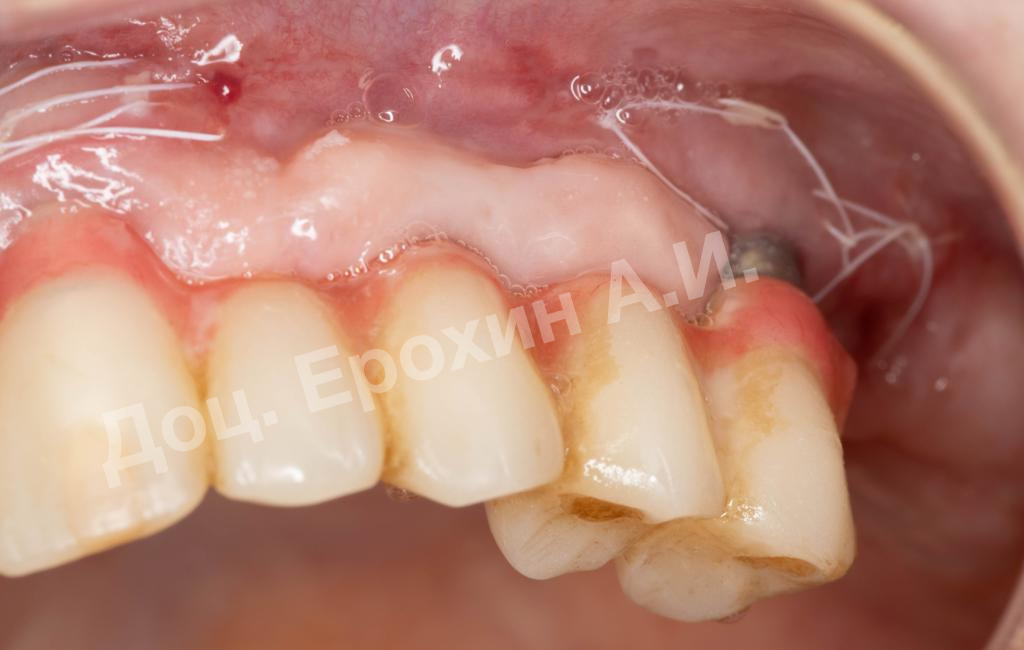

В результате, спустя 10 лет мы видим, что единственная часть десны в области имплантации, не затронутая рецессиями, — это зона, где была проведена трансплантация десневого фрагмента. С целью стабилизации имеющихся имплантатов на повторном приеме была проведена вестибулопластика по Кларку с фиксацией мягкотканных мукотомов, фрагментов эпителия с неба, зафиксированных швами.

В данном клиническом случае мы можем наблюдать эффект так называемого наползающего прикрепления (creeping attachment), когда десна после удаления момента натяжения начинает сама наплывать на ранее оголенные корни зубов и имплантаты.

На фото видно, что в первом сегменте с 2.5-3 мм оголение корня осталось меньше 1 мм, в области имплантата 21 рецессия самоустранилась, а в области имплантата 26 рецессия до операции была 4.5 мм, а после сократилась до 2 мм.